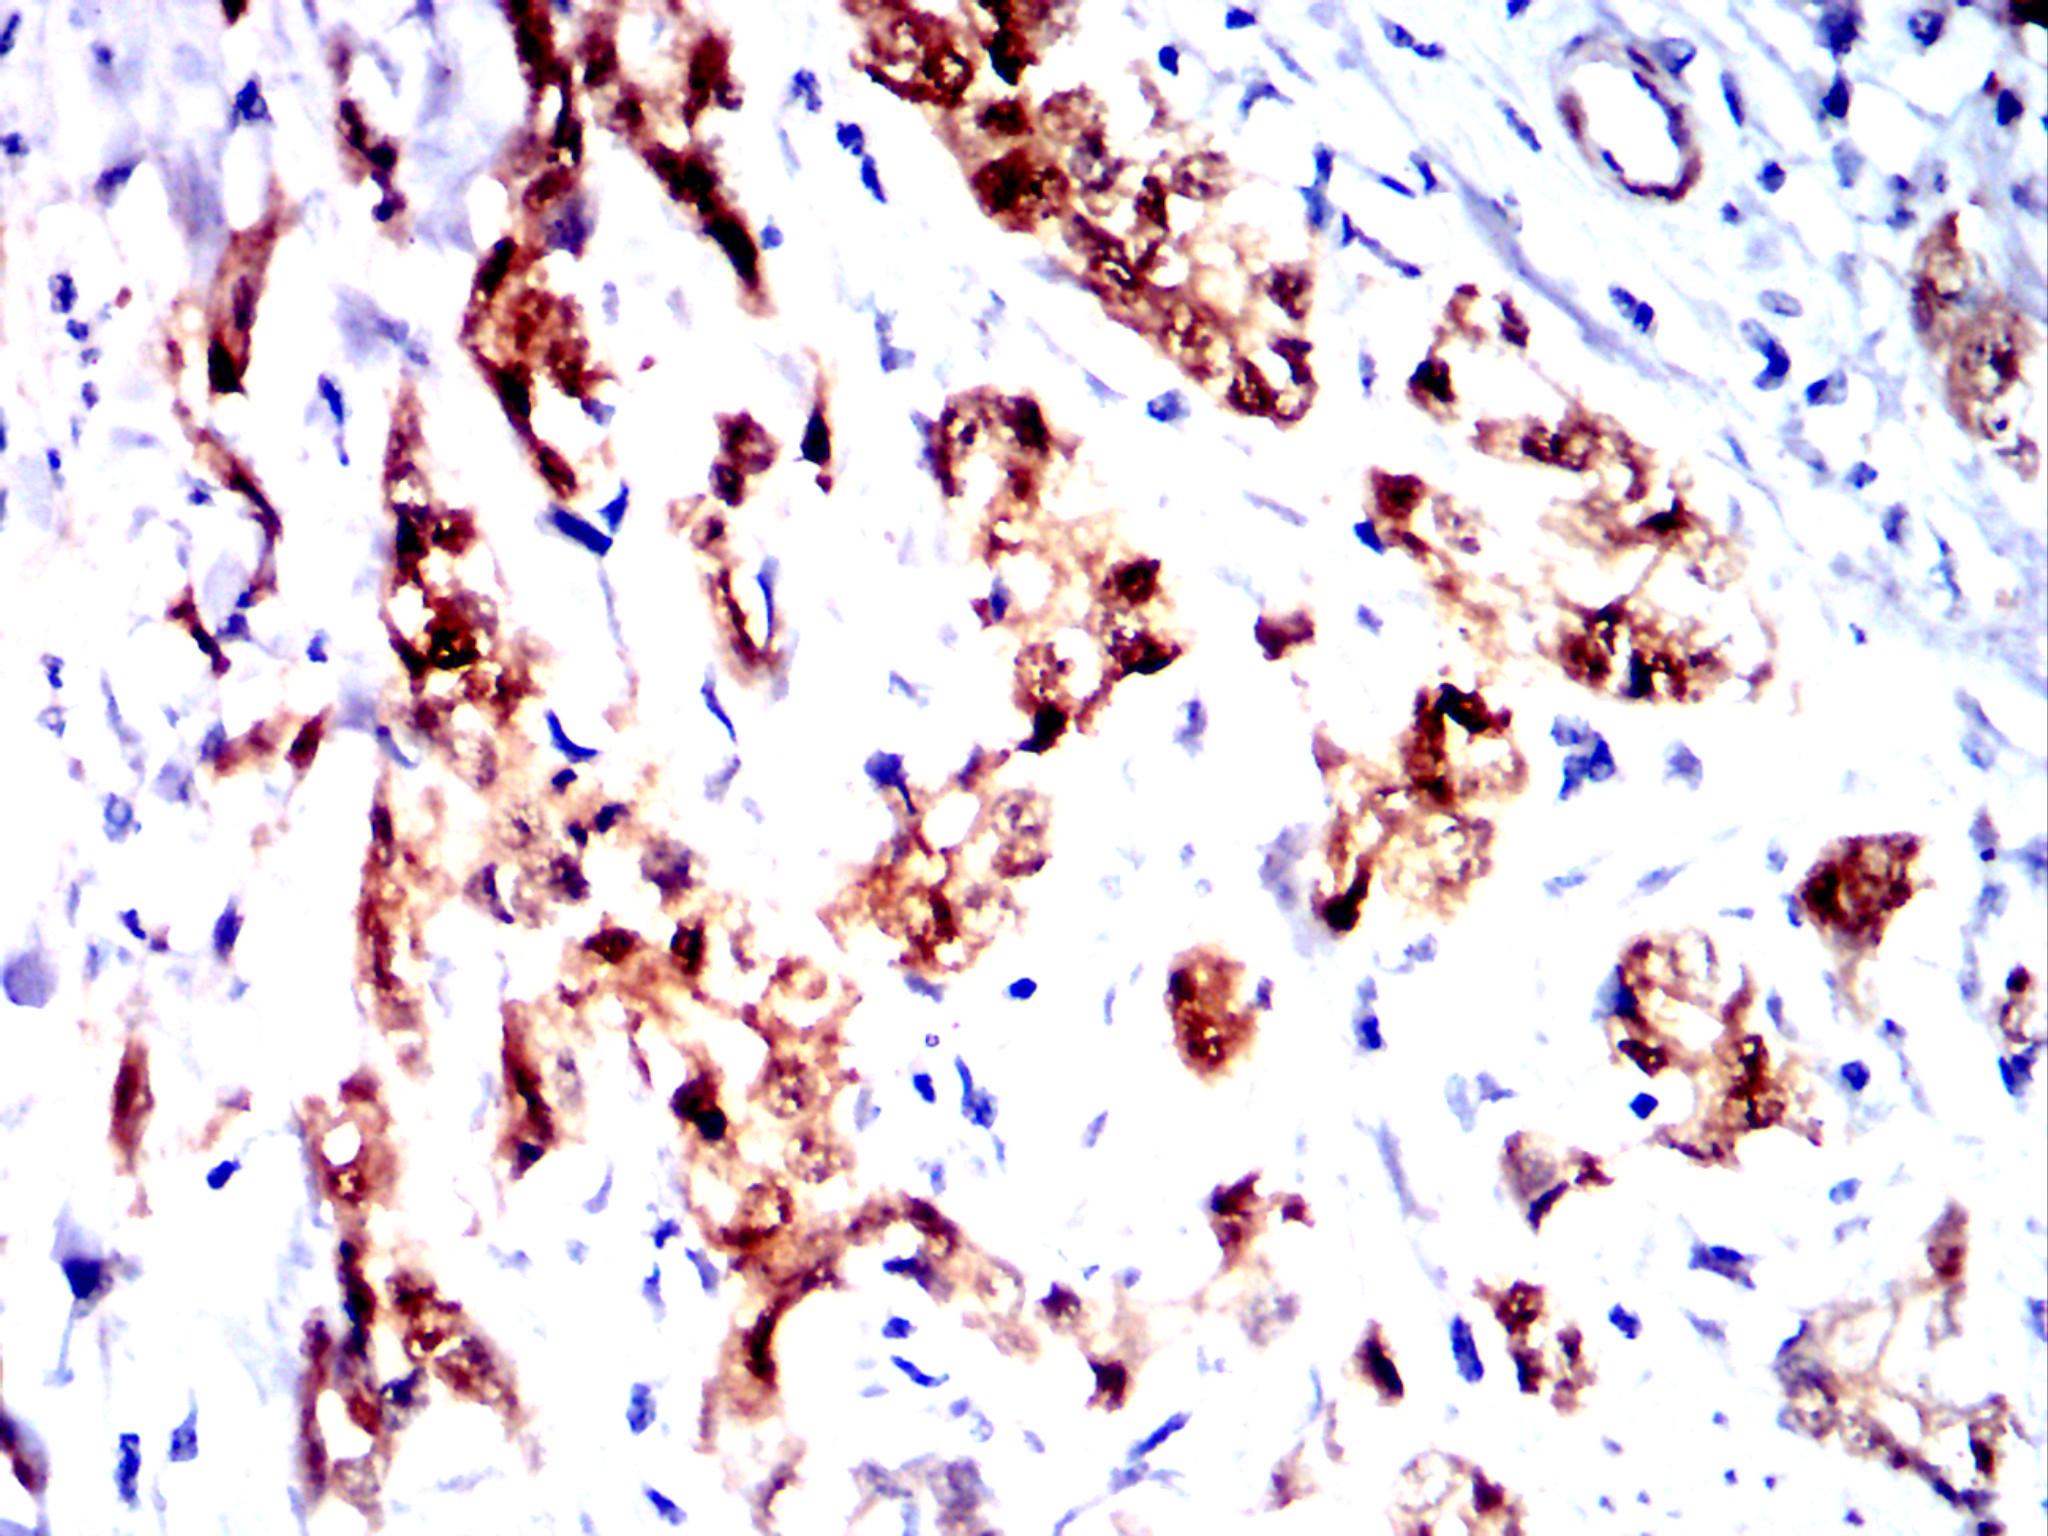

分类: 科研抗体货号: 32454别名: CEA;CD66e应用: IHC反应种属: Human